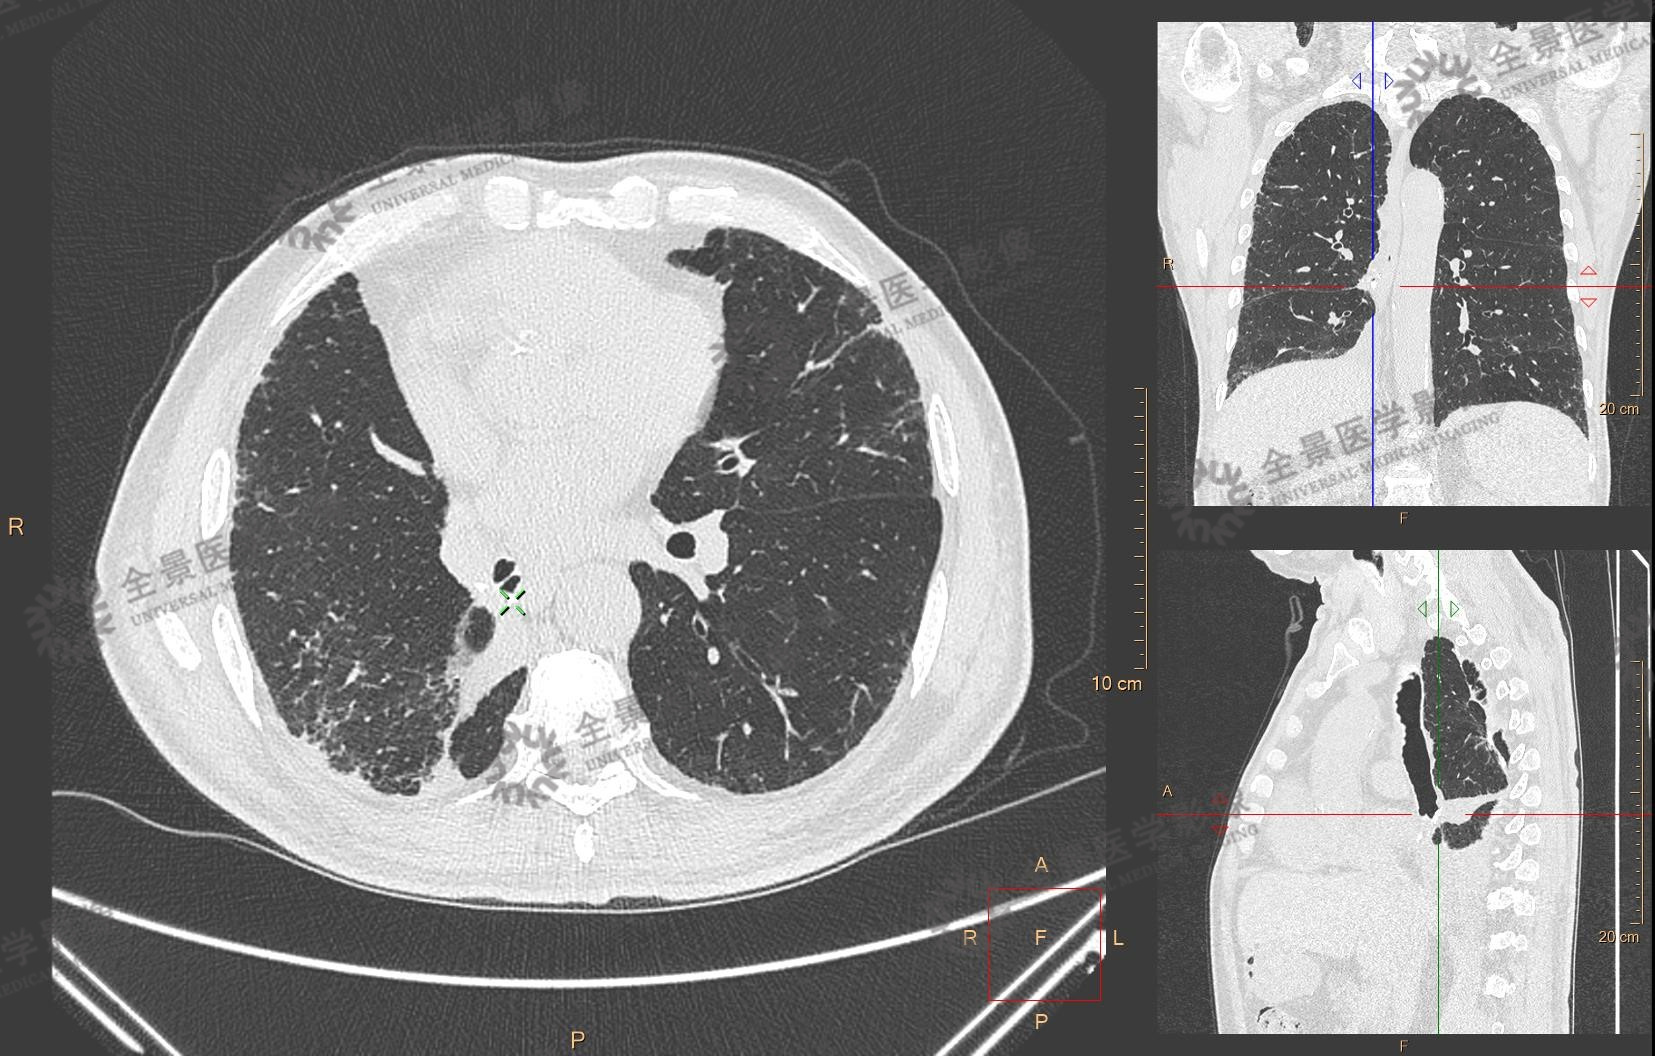

术后三个月,蒋老先生再次选择天津全景进行术后CT复查。桃李不言,但行动生发出的信任和替患者的喜悦交织在一起,是这个春天里最让人感动的画面。

术后CT复查 右肺下叶切除